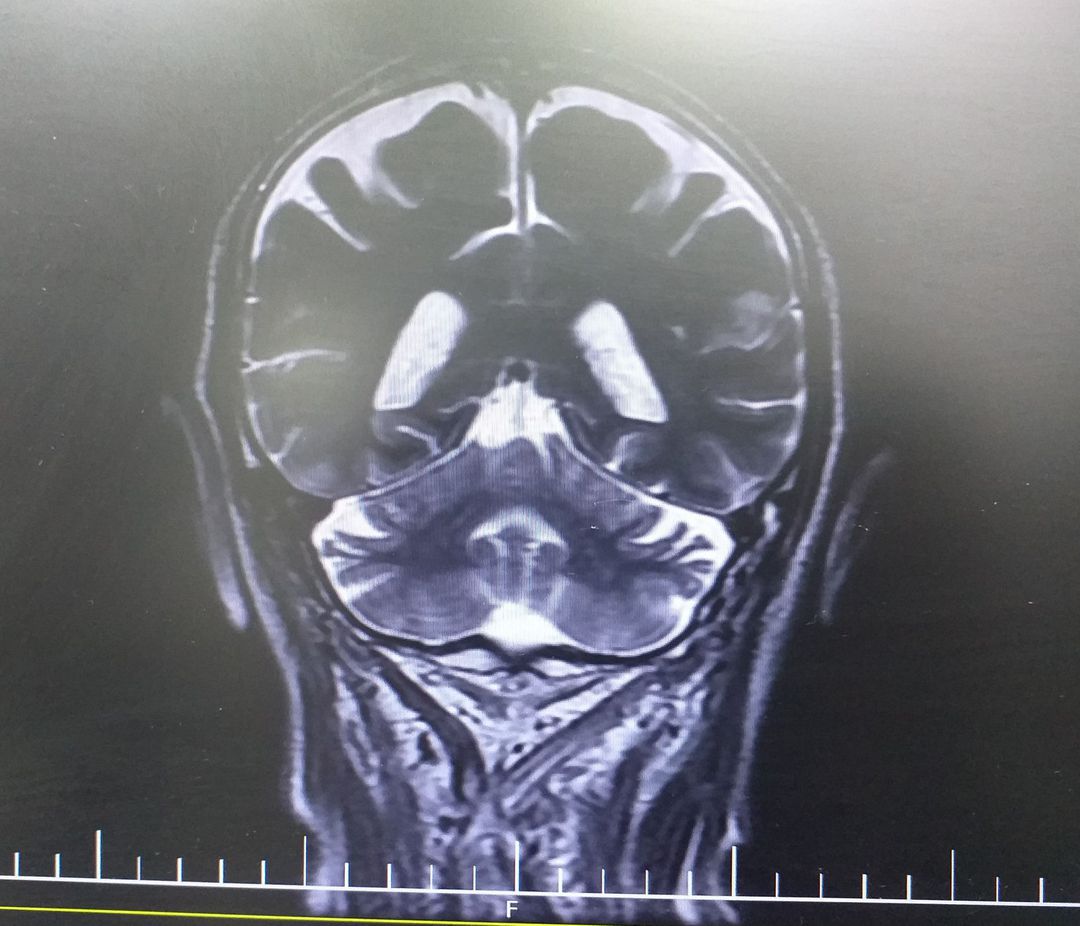

What is your diagnosis?

Locked in syndrome